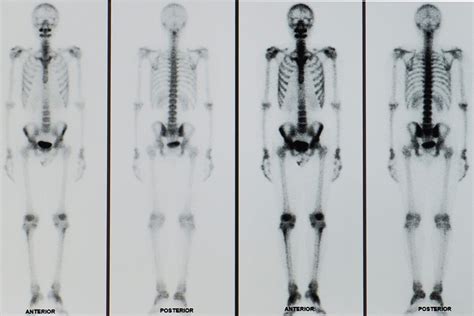

El Patrón "Superscan"

En casos graves, la gammagrafía puede presentar el patrón de "superscan", caracterizado por una intensa y difusa captación en todo el esqueleto, con ausencia de fondo y, generalmente, de las siluetas renales. A diferencia del "superscan" de origen metastásico, la captación en el cráneo es constante en el "superscan" de origen metabólico.

La gammagrafía ósea tiene un valor limitado para el diagnóstico directo del hiperparatiroidismo primario, pero es útil para valorar la extensión de la afectación esquelética. Si la gammagrafía es normal, la radiología también lo es. La intensidad de la hipercaptación del trazador puede correlacionarse con la gravedad de las alteraciones radiológicas. Las apariencias gammagráficas varían desde la normalidad hasta un incremento generalizado de la captación, incluido el patrón de "superscan". Este patrón se observa con mayor frecuencia en el hiperparatiroidismo, especialmente secundario, y en la osteodistrofia renal (ODR).

La gammagrafía ósea puede mostrar un patrón de "superscan", especialmente en el hiperparatiroidismo secundario y la ODR. En casos de hiperparatiroidismo terciario, que cursa con activación autónoma de las glándulas paratiroides, pueden observarse alteraciones óseas más dramáticas, como tumores óseos metastásicos. La ablación del adenoma puede ser una estrategia terapéutica en estos casos.